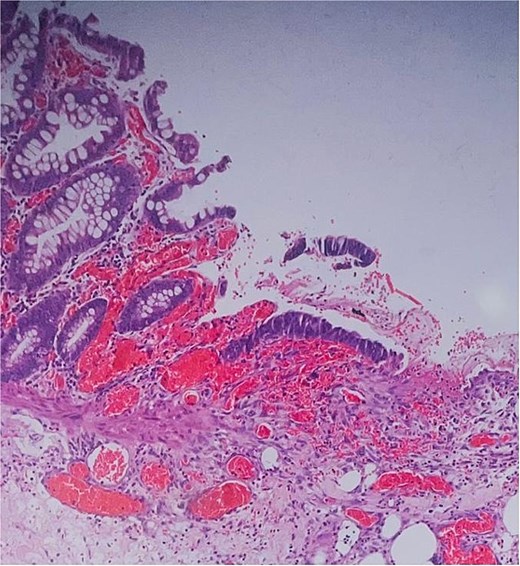

Histological evaluation confirmed acute necrotizing colitis with transmural inflammation and granulation tissue (Figs 4 and 5). Hepatic cyst biopsies revealed benign biliary duct cysts with cystically dilated bile ductules.

Histopathology: complete surface ulceration with granulation tissue (H&E, × 40).